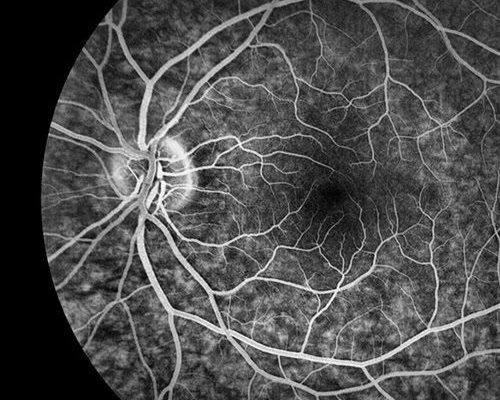

Mapeamento de Retina: um cuidado essencial para a saúde dos seus olhos

O mapeamento de retina é um exame fundamental para avaliar a saúde ocular de forma